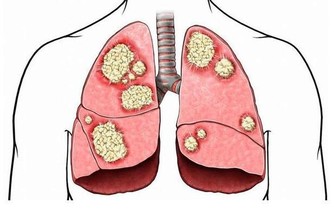

高血壓誘發腎衰竭,臨床大多表現在代謝產物瀦留,水分,電解質,酸鹼代謝物失衡,繼而導致腎小球過濾功能下降,以及良性甚至惡性的小動脈腎硬化。如果不及時進行調整,後續發展成為慢性腎衰竭的風險就會增加。

換句話說,我們可以將腎衰竭看做是高血壓惡化的並發症的一種。而拒絕正常的服藥流程,就相當於無限擴大了高血壓惡化的風險。